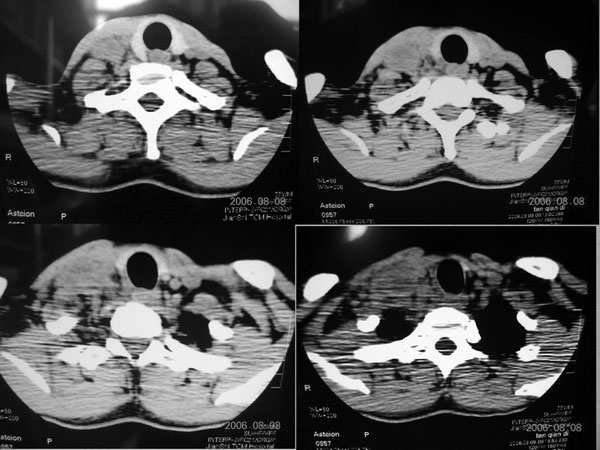

患者,谭××,男,35岁,右颈部肿痛一周,体温39度。增强待续,伪影大,对不起,请大家凑合……

生长于颈部2血管之间多房样壁强化明显。

生长于颈鞘部2血管之间的病灶,环状强化明显,见分隔。

生长于颈部2血管之间多房样壁强化明显,结合临床右颈部肿痛一周,体温39度,

右颈部肌肉、血管间隙内可见不规则肿块,强化后呈多房性,间隔及壁线样强化,考虑颈部脓肿。